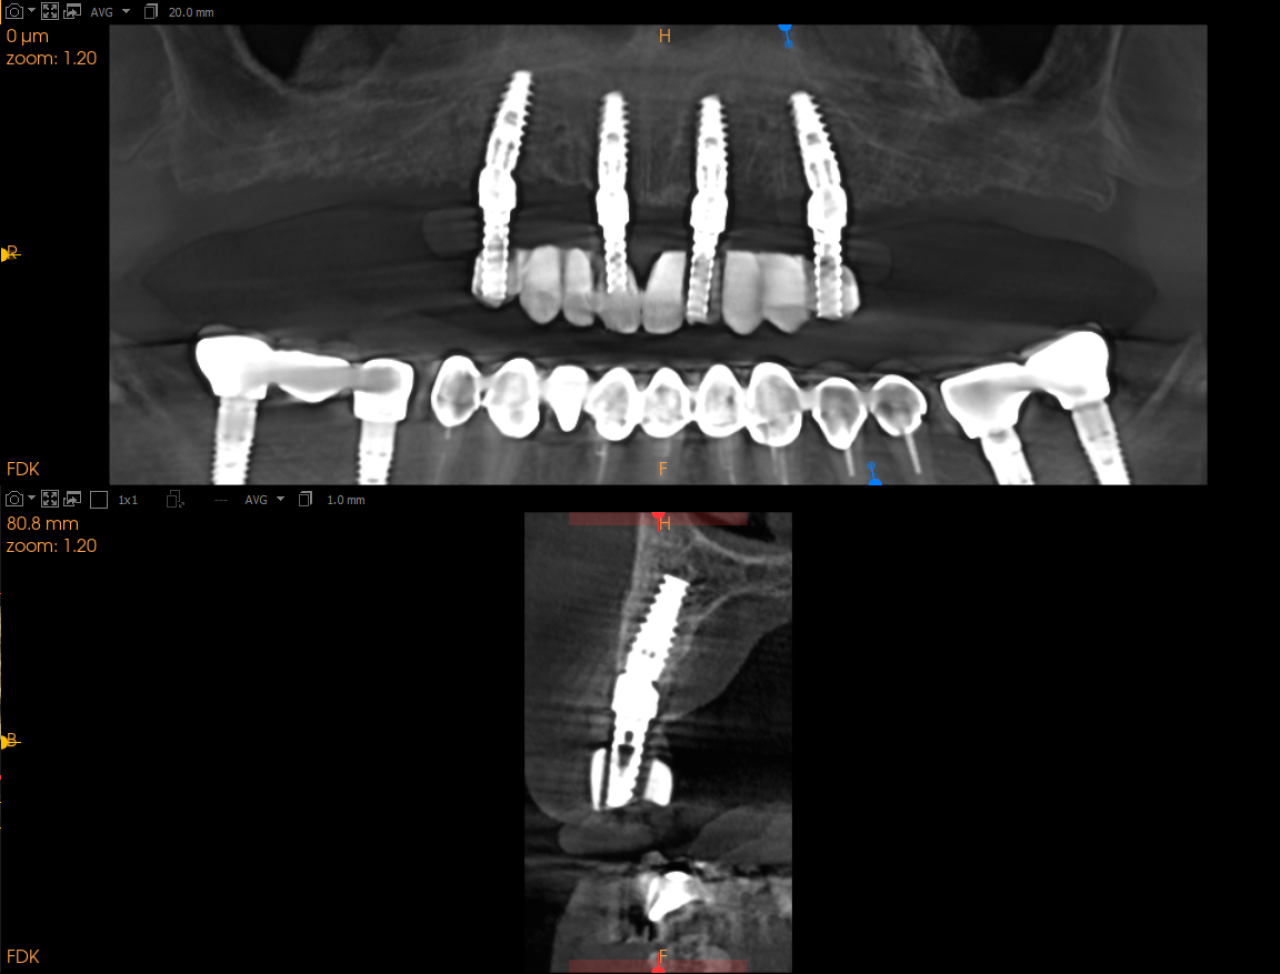

CBCT

CBCT (konusno-zračna kompjuterska tomografija) predstavlja suvremenu radiološku metodu koja omogućuje trodimenzionalni prikaz struktura čeljusti, zuba i okolnih tkiva s iznimnom preciznošću.

U ordinaciji Microdental pacijentima je dostupna CBCT dijagnostika na licu mjesta, bez potrebe za odlaskom u druge ustanove. Ova vrsta snimanja pruža detaljan uvid u anatomiju korijena zuba, poziciju impaktiranih zuba, stanje koštanog tkiva te se često koristi kod implantološkog planiranja, endodontskih tretmana i kirurških zahvata.

Implantologija

Dentalni implantat je kirurška komponenta koja se postavlja u čeljusnu kost i služi kao potpora za krunice, mostove, proteze ili ortodontsko sidrište. Implantat je građen od titana, a njegova je površina obrađena na način da privlači koštane stanice. Takav biološki proces je temelj moderne implantologije i naziva se oseointegracija.

Najprije se postavlja implantat te se čeka minimalno 3 mjeseca kada dolazi do oseointegracije, nakon čega je implantat spreman za opterećenje protetskom nadogradnjom.